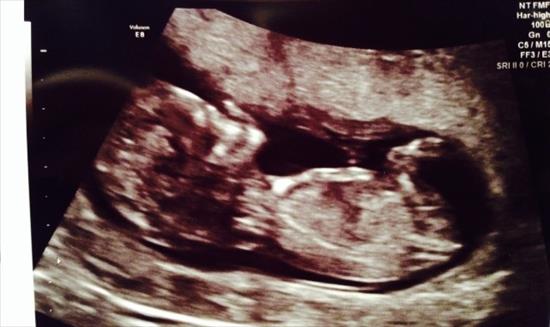

Can anyone see the nub in this ultrasound photo taken 12w 1d ? Predictions welcome !!

I don't see a nub.